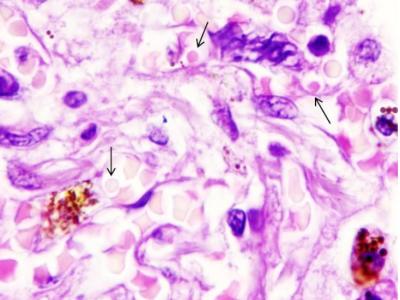

C’est pour cette raison que les cellules du système immunitaire et des mégacaryocytes, de très grandes cellules de la moelle osseuse, ont été trouvées dans les tissus de divers organes. Normalement, les mégacaryocytes produisent des plaquettes sanguines, qui sont responsables de la coagulation du sang, mais avec le COVID-19, ils coagulent le sang dans les vaisseaux sans aucune nécessité.

Ainsi, la fibrose pulmonaire n’est qu’une manifestation plus évidente du COVID-19, causée elle-aussi par un excès de mégacaryocytes dans la circulation sanguine et des processus similaires peuvent se produire dans les tissus de tous les organes parenchymateux (denses), à savoir les poumons, le foie, la rate, les reins, le pancréas et la thyroïde.

Ces scientifiques ont vérifié ces processus sur des échantillons de poumons de 79 patients décédés du COVID-19.